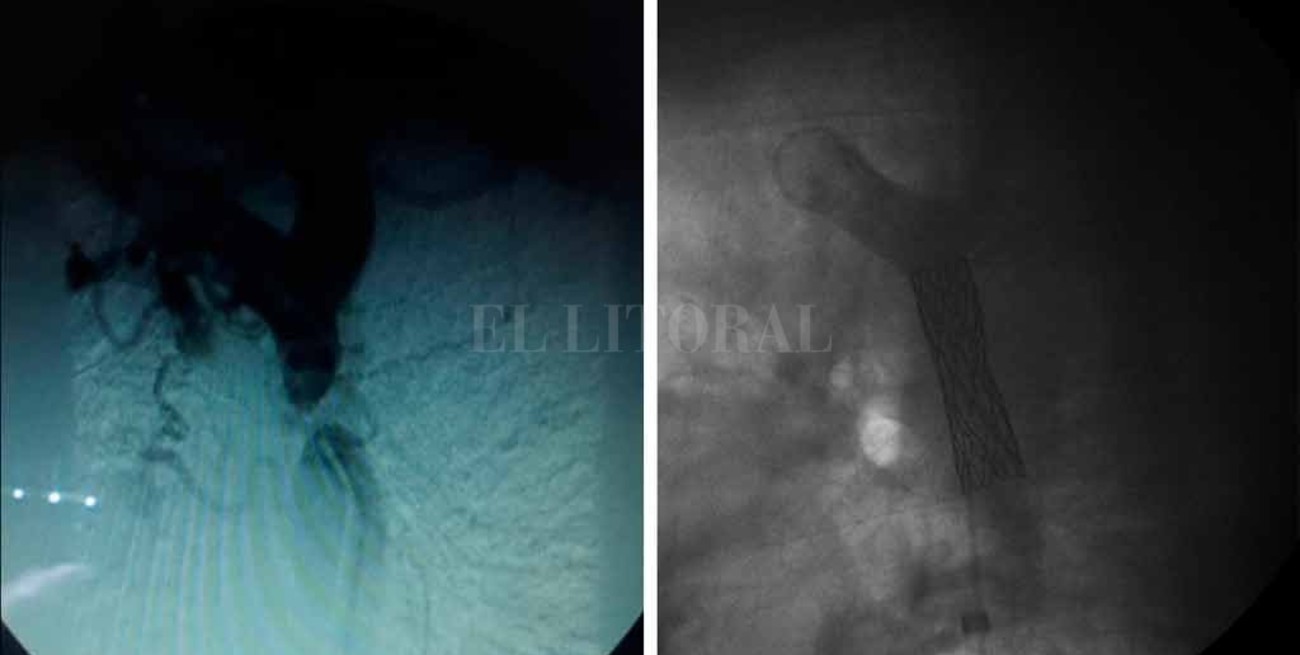

La operación empezó con dos pequeñas punciones: una en la arteria femoral derecha, en la pierna, y otra en la arteria radial en el antebrazo, para poder ingresar los catéteres —son como “tubitos” de 2 milímetros— y llevarlos hacia la zona de la obstrucción, que en el caso de las coartaciones siempre está cerca del ductus arteriosus.

Es el proceso más largo de la intervención y demandó casi 3 horas. El margen de error es mínimo. “Si se perfora la aorta y se produce una hemorragia, el paciente muere en menos de cinco minutos por la pérdida de sangre”, advirtió Birollo, que no pudo participar de la operación, luego de haber realizado muchas gestiones para organizarla, porque la fecha coincidió con un curso de capacitación en Colombia.

Cuando la obstrucción se liberó, comenzó la segunda etapa: “inflar el balón” para ampliar la arteria y colocarle a Darío, con un cateter más grande (1 centímetro), un stent (la angioplastía propiamente dicha). Es una pequeña malla metálica que se utiliza para mantener la arteria abierta y normalizar el flujo sanguíneo. Esta parte llevó unos 40 minutos más.